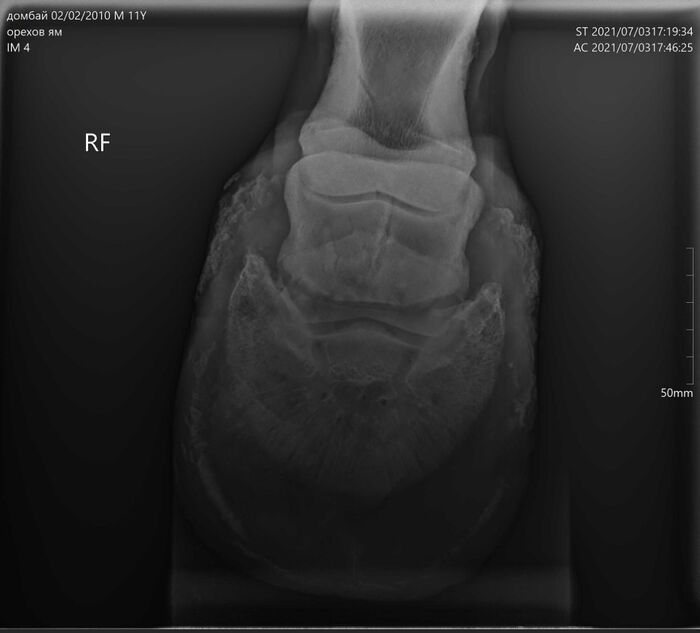

На этих x-ray снимках Домбай.

У него артроз (или артрит, я такой себе врач) пальчиков на руках.

Плюс косточка в копыте подходит очень близко к краю.